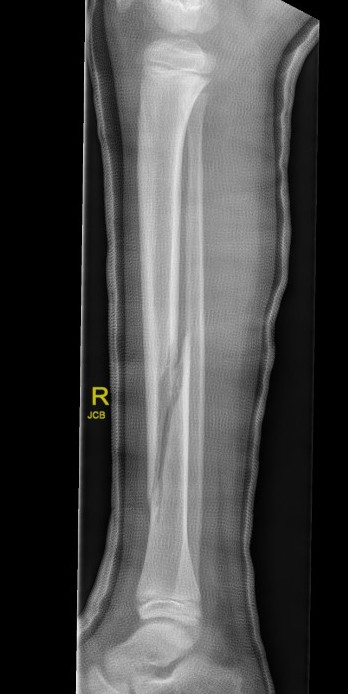

Displaced Tibial Shaft Fractures

Acceptable reduction

- varus / valgus < 5o

- anterior / posterior < 5o

- rotation 5o

- shortening 10 mm